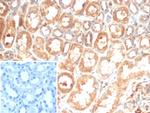

IL-6 (Interleukin-6)/Interferon beta-2 (Hybridoma Growth Factor) Antibody in Immunohistochemistry (Paraffin) (IHC (P))